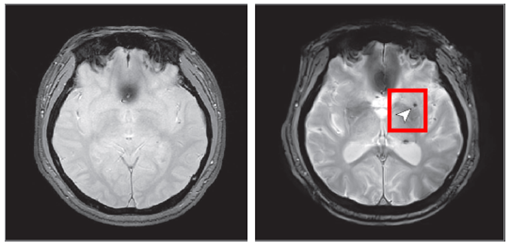

研究によると、睡眠時無呼吸症候群がない人々の脳微小出血発生率は3.3%程度だったが、中等症以上の睡眠時無呼吸症候群患者ではこの割合が7.25%に跳ね上がり、約2.14倍増加したことが示された。つまり、時間が経つにつれて繰り返される睡眠中の呼吸停止が脳血管を直接損傷する可能性があることを意味している。

微小脳出血は脳内の小さな血管が損傷して発生する微細な出血で、今後の脳卒中などの深刻な血管疾患を予告する初期指標として知られている。